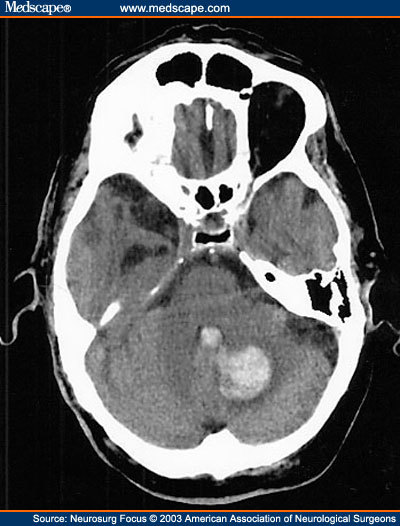

DDx for posterior fossa tumour in a child includes?

1: Medulloblastoma 2: Cerebellar astrocytoma 3: Ependymoma 4: Brain stem glioma NB: Haemangioblastoma is the commonest lesion in adults

1: Where do Medulloblastoma’s arise from? 2: How can they be differentiated from an astrocytoma?

1: the Cerebellar vermis 2: They are HYPERdense on an unenhanced CT cf pilocytic astrocytoma which are hypo